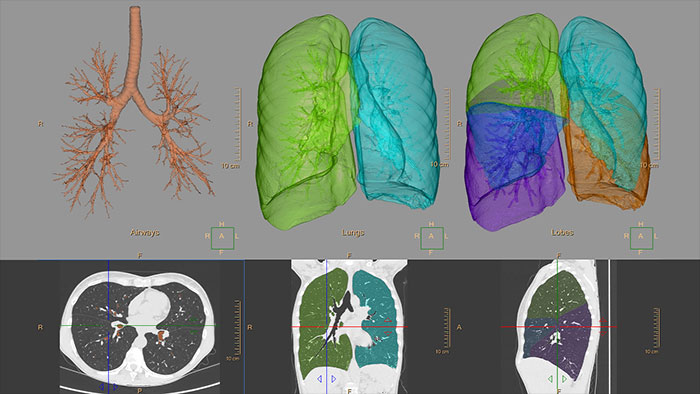

The clinical application helps visualize and quantify the destructive process of diffuse lung disease (e.g. emphysema), providing a guided workflow for airway analysis, reviewing and measuring airway lumen, and assessing air trapped.

CT COPD helps quantifiably track the destructive process of diffuse lung disease (emphysema) and helps localize specific areas of the lung that have been affected.

An advanced imaging package for the segmentation, quantification and follow-up of physician-indicated lung nodules, that can be used in both diagnostic and screening evaluations, supporting Low Dose CT Lung Cancer Screening.*